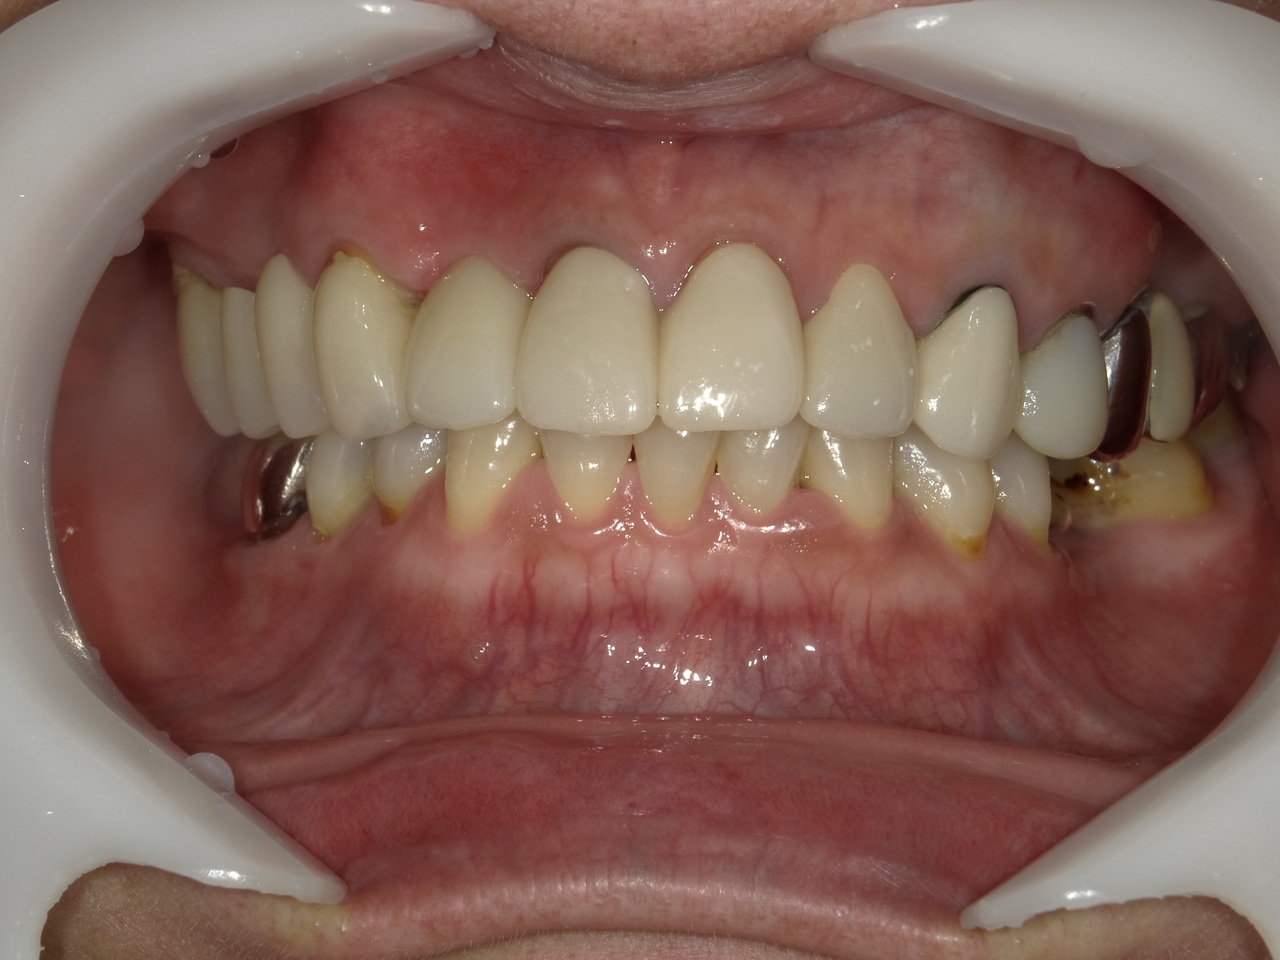

After

枚方市のインプラントの症例

E・S様 女性 60代

患者様の症状としては、左上5番の排膿と重度の歯の動揺、重度の骨吸収、左上3番、中程度の骨吸収と中程度の歯の動揺、自発痛がありました。

治療法としては、左上3456にブリッジ治療が行われていたが、左上5の骨吸収と排膿を認めるために抜歯を行った2か月後に、患者様は、インプラント治療を希望。左上3の骨吸収と動揺も認めていたために、左上3を保存しても将来的な抜歯が予想されたため、左上3抜歯しての左上345の3ユニット式ブリッジ治療の計画を立てインプラント手術を行っています。患者様は、前歯がないことを気にされていたため、左上3番の抜歯と同時の仮歯製作と左上4番暫間インプラントにての仮歯製作を手術と同時に行っています。また、左上3番の歯肉退縮を予防するために、ご自分の歯の一部を温存するルートメンブレンテクニックを行っています。左上5に関しては、既存骨が3mm程度しかないので、グラフトレスサイナスリフトを施行して、表面の骨吸収した部分に骨補填材填入して、ボリュームを維持させていただいています。最終的な3ユニットブリッジは、ジルコニアで製作しています。補綴物の製作に関しては、オールデジタルで行っています。

治療結果は、患者様の希望通り、見えるところの歯がない状態なく、治療を終えることができたことと、また、グラフトレスサイナスリフトを施行することにより、従来のサイナスリフトを施行した場合と比較して、6時か月以上早く治療を終えることができたことと、ルートメンブレンテクニックを行うことで、歯肉退縮を少なくでき、自然な見た目で、最終補綴物を装着できました。従来のGBRやサイナスリフトを行わなかったことにより、短時間で、低侵襲に治療を終えることができ、審美面と機能面の回復を行うことができました。